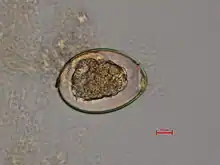

The adult worm is composed of three fairly distinct morphological segments: the scolex (head), the neck, and the lower body. Each side of the scolex has a slit-like groove, which is a bothrium for attachment to the intestine. The scolex attaches to the neck, or proliferative region. From the neck grow many proglottid segments which contain the reproductive organs of the worm. D. latum is the longest tapeworm in humans, averaging ten meters long. Unlike many other tapeworms, Diphyllobothrium eggs are typically unembryonated when passed in human feces.[4]